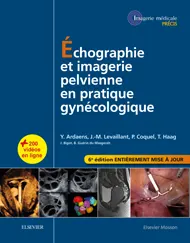

Pertes vaginales anormales

Les vulvites sont fréquentes chez la fillette, souvent récidivantes. Les vulvovaginites sont plus rares avec des leucorrhées plus ou moins abondantes, parfois striées de sang. Dans les deux cas, l’infection est liée à des erreurs d’hygiène avec des germes variés non spécifiques. Un corps étranger est à l’origine de 5 % des vulvovaginites, surtout entre 4 et 7 ans. Un cliché d’abdomen sans préparation peut rechercher un corps étranger radio-opaque. L’échographie peut montrer un écho dense intravaginal (fig. 4-32) mais l’examen clinique reste indispensable pour le diagnostic et l’extraction de l’éventuel corps étranger.

L’existence de saignements vaginaux doit faire pratiquer d’emblée une échographie afin de rechercher :

■ un corps étranger intravaginal ; ■ un rhabdomyosarcome du sinus urogénital ; ■ une puberté précoce.